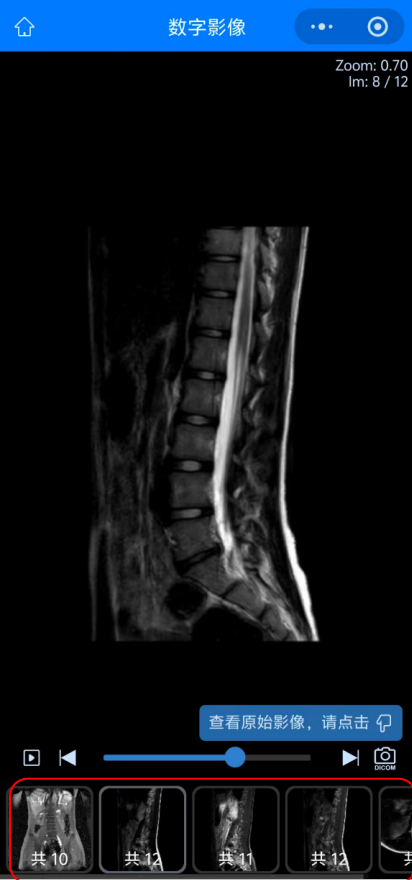

05 而點(diǎn)擊“查看影像”后查看到的患者的影像圖像,可以選擇下方紅色方框內(nèi)不同影像檢查或圖象處理方法來查看不同影像圖像。

09 如何進(jìn)行圖像下載:首先在查看圖像功能內(nèi)點(diǎn)擊右下方照相機(jī)圖標(biāo),進(jìn)入“查看原始影像”。